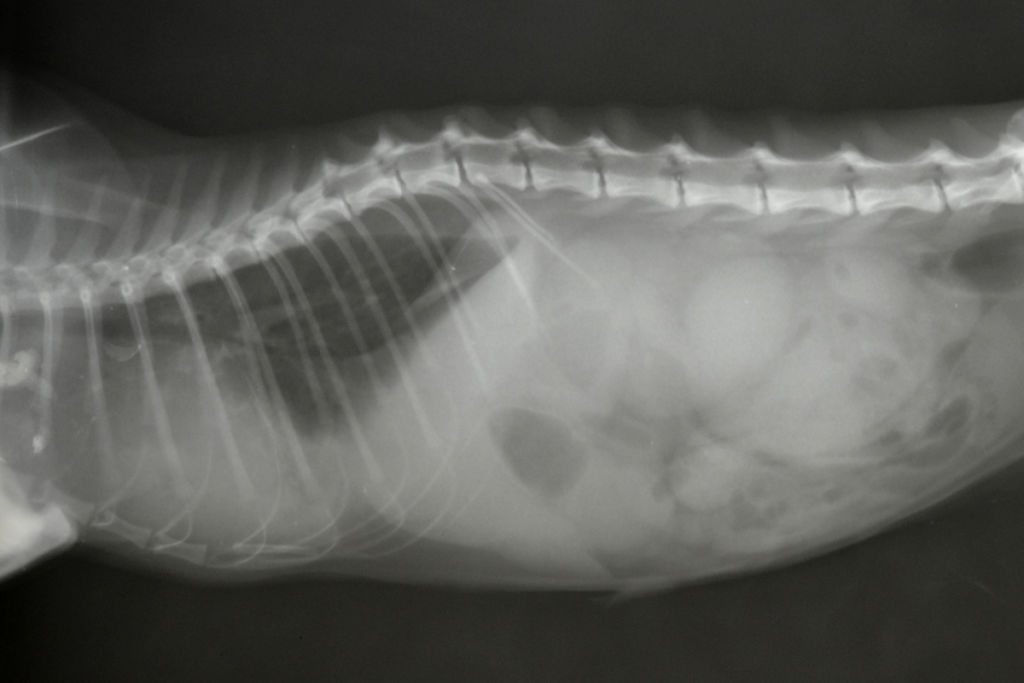

А потому ветеринары всегда берут анализы крови и мочи, при необходимости проводят рентгенологическое и ультразвуковое исследование. Ультразвук брюшной полости (сонограмма) позволит оценить состояние печени, селезенки, внутренних лимфатических узлов и кишечника.

Рентген грудной клетки позволит выяснить, не вовлечены ли в процесс легочные лимфатические узлы. Аспират костного мозга очень важен: он дает возможность выявить опухолевые клетки, а также оценить способность органа к воспроизводству нормальных составляющих крови. Когда ветеринар получит результаты всех исследований, он сможет назначить наиболее подходящее лечение лимфосаркомы у кошек.

Лимфома почек и средостения у кота, подтверждена цитологически после эвтаназии и вскрытия